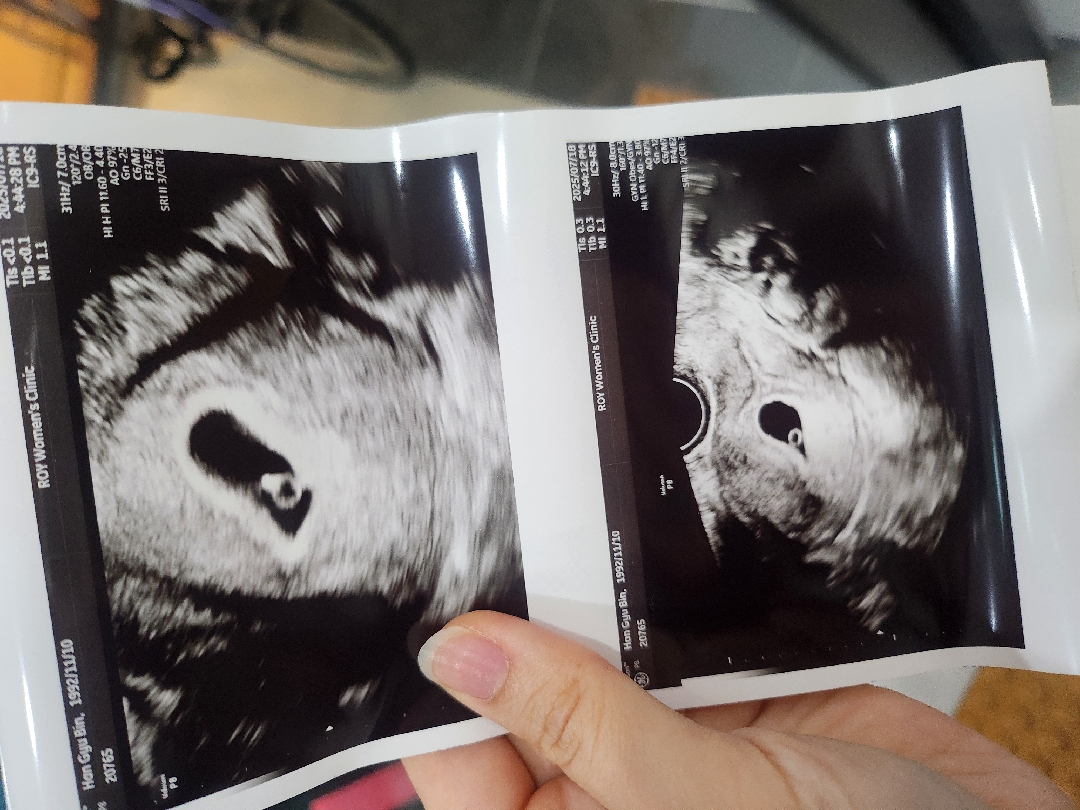

지난주 토요일에 아기집만 확인하고 난황도 안보였어서 괜히 걱정되고 불안해서 폭풍 검색하다가 (4주 후반에서 5주 초반 예상) 오늘 못참고 초음파 갔더니 어느새 아기집 엄청 커지고 다이아반지까지 보고ㅜㅜ 심장소리도 들릴까 하고 봐주시더니 작고 소중한 심장소리가 두근두근 하더라고요 ㅠㅠ 5주 5일차 정도인것같다고 하셨어요 (네이버 주수상으로는 6주0일차) 이번주 내내 야근하고 힘들었어서 걱정했는데 다행히 아가는 착실히 집짓고 있었다니 너무 고맙고 기특해서 눈물이 났어요🥹 + 아 그리고 쓰리라인 임테기가 어제 딱 역전했는데 딱 맞았어요! 신기한거 투성이에요 진짜